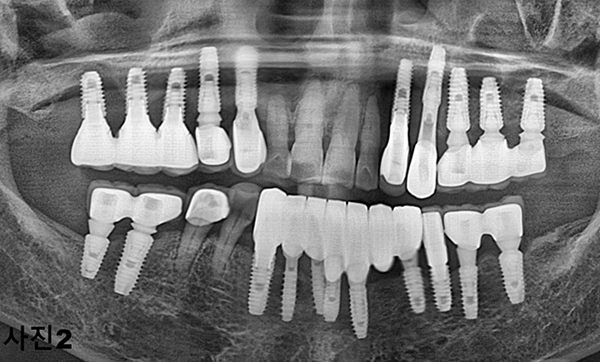

2025년 10월 아래턱이 심하게 붓고 너무나도 아픈 모습으로 내원하신 70대 여성분 (사진1)과

X-ray 촬영 (사진2)후에 구강검진을 하여보니 임플란트를 식립한 모든 부위에 심한 부종과 통증이 그리고 고름이 흘러나오고 있었다.

(사진3) 그 부위를 열어보니 너무 촘촘히 박히고 임플란트를 제대로 식립 못하여 임플란트의 나사선들이 잇몸뼈에 제대로 들어가 있지 못하고 밖으로 노출되어 있었다.

저렴한 임플란트를 선전하는 병원들에서 임플란트를 필요이상의 박리다매의 현상을 보여주고 있다.